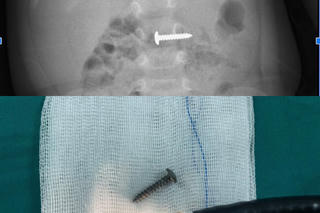

từ khóa: #Nuốt đinh vào bụng